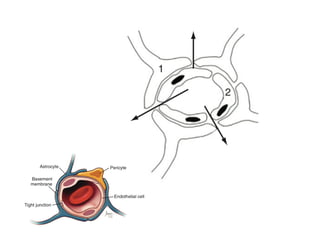

• Mechanisms

• Blood-tumor barrier has abnormal micro vessels

that lacks of tight junctions cause plasma leakage

into brain’s extracellular space

• Mechanisms • Blood-tumorbarrier has abnormal micro vessels that lacks of tight junctions cause plasma leakage into brain’s extracellular space • Macromolecular protein produced by tumor has been identified as vascular permeability factor (VPF) and vascular endothelial growth factor (VEGF)